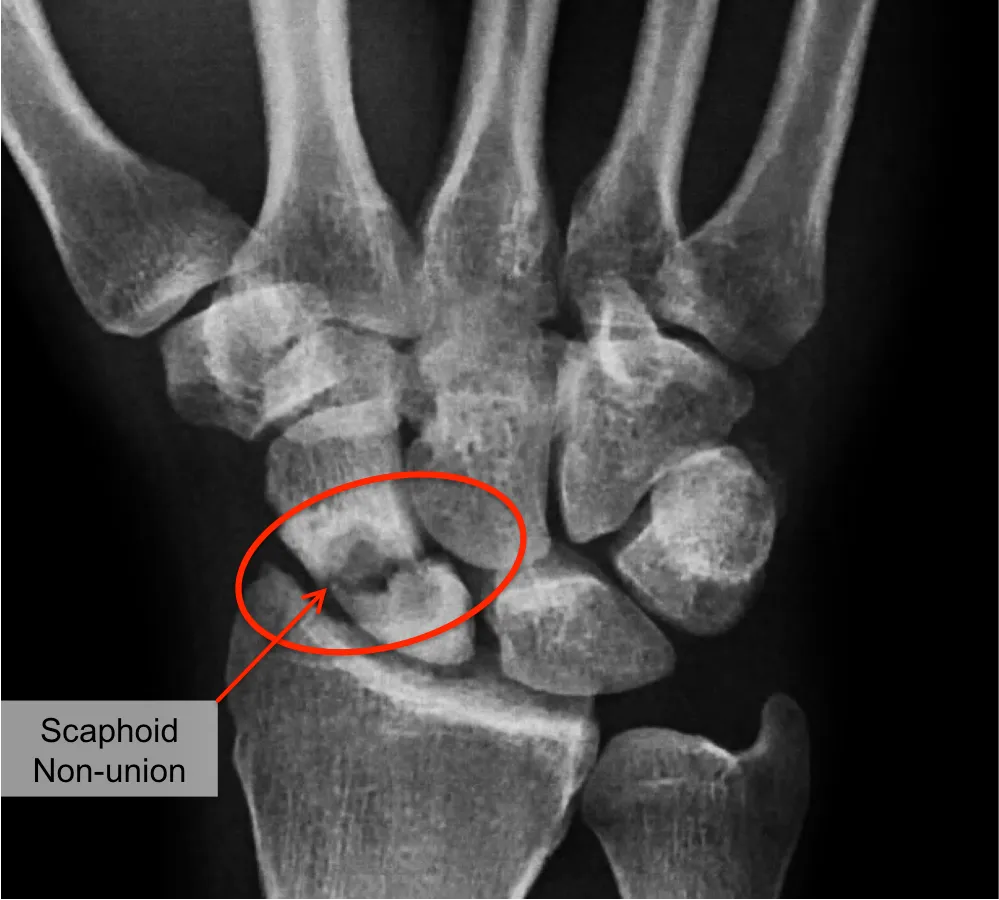

- Röntgenfoto: Er worden gerichte foto’s van het scaphoid gemaakt (in meerdere posities). Hierop is doorgaans te zien dat de breuklijn nog aanwezig is en er geen nieuwe botbrug tussen de stukken is gevormd. Soms staan de delen van het scaphoid wat uit elkaar of onder een hoek.

- CT-scan: Een CT-scan is de gouden standaard om een scaphoid non union te beoordelen. Hiermee kan de mate van botgenezing precies worden bekeken, inclusief eventuele verharding van de fractuurvlakken (sclerose) en hoe ver de fragmenten uit elkaar staan of verschoven zijn.

Een scaphoid non-union betekent dat een gebroken scaphoid (ook wel scheepsvormig handwortelbeentje genoemd) niet is vastgegroeid. Het scaphoid is een klein botje aan de duimzijde van de pols dat vaak breekt bij een val op de hand. Normaal hoort zo’n breuk binnen 6-8 weken te genezen. Bij een scaphoid non-union gebeurt dit niet: de twee botstukken van het scaphoid groeien niet meer aan elkaar, waardoor een blijvende breuklijn (pseudartrose) in het bot ontstaat. Dit kan komen doordat de breuk gemist of onvoldoende behandeld werd, of door slechte doorbloeding van het gebroken deel (met name bij een breuk in het proximale deel, dichtst bij de onderarm, van het scaphoid is de bloedvoorziening beperkt). Het resultaat is een instabiel polsgewricht dat na verloop van tijd kan leiden tot slijtage (artrose) in de pols.